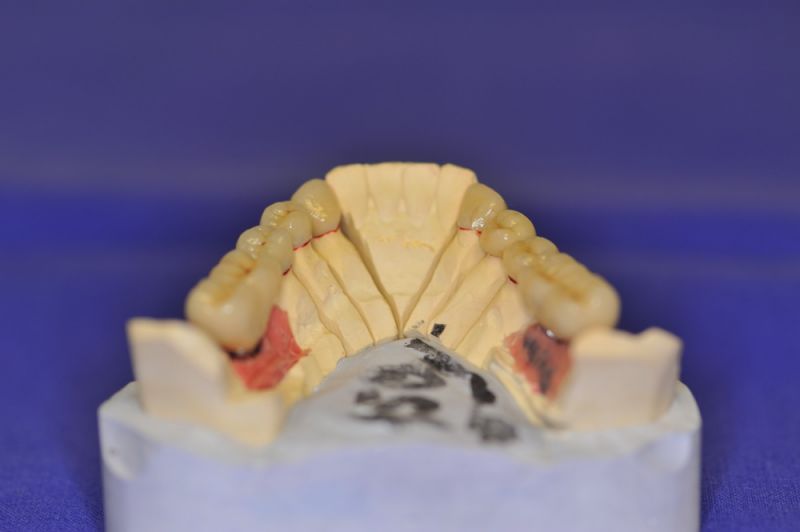

Mit dem heutigen Tag geht eine der technisch schwierigsten und anspruchsvollsten Arbeiten zu Ende, die im CMD-CENTRUM-KIEL jemals erstellt worden ist. Dabei sind es nur 10 Kronen, die benötigt werden, um die starken Kopf- und Gesichtsschmerzen der Patienten zu beseitigen.

Die Lösung einer Vielzahl technischer Probleme, die vorrangig verursacht waren durch:

1. Notwendigkeit einer implantatgestützten Kronenversorgung mit der Vorgeschichte, dass die Patientin eine Vielzahl von Behandlern aufgesucht hatte, die eine Implantation im Unterkiefer als nicht durchführbar einschätzten.

4. Notwendigkeit die Mundhygienefähigkeit der Arbeit auch unter sehr beengten Verhältnissen zu schaffen, um der Arbeit eine günstige Prognose mitzugeben.